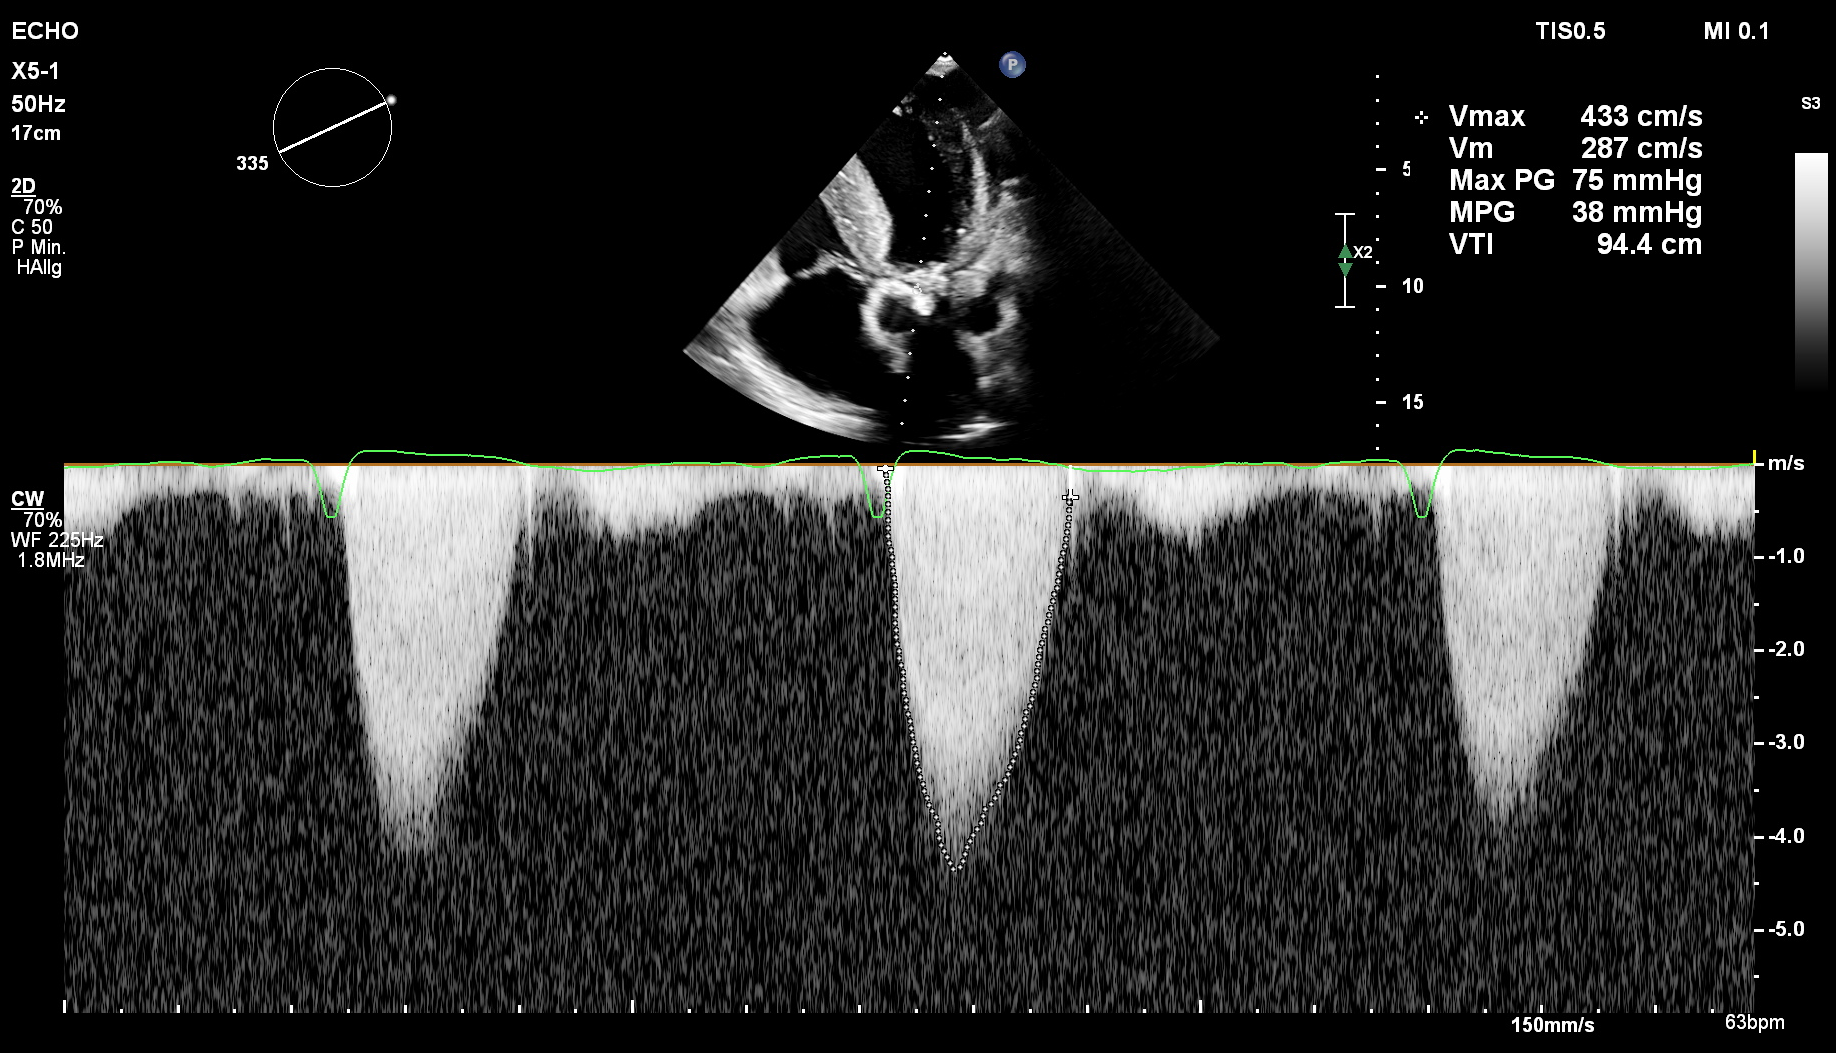

AoV-Stenose

Erstdiagnose einer schweren Aortenklappenstenose mit verminderter Separation der ausgeprägt sklerosierten Klappen bei einem Hämodialyse-Patienten mit in den letzten Tagen progredienter Dyspnoe. Die weitere Evaluation erfolgt mittels Dopplersonografie.

cw-Doppler: AoV-Stenose

subkostale Schnittebene

Darstellung der AoV-Stenose im cw-Doppler.